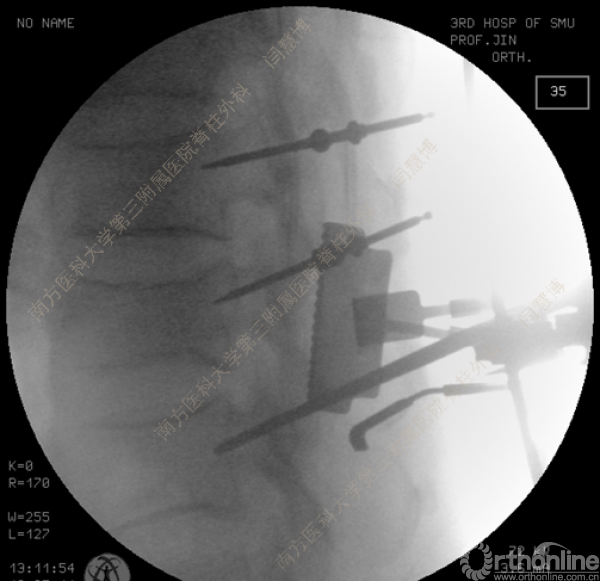

胸腰椎骨折是指由于外力造成胸腰椎骨质连续性的破坏,在如车祸、高处坠落等意外事故中,是最常见的脊柱损伤。老年患者由于本身存在骨质疏松,甚至有可能因为一些如滑倒、跌倒等低暴力因素导致胸腰椎骨折。胸腰椎骨折患者常合并神经功能损伤,且由于致伤因素基本为高能损伤,常合并其他脏器损伤,这为治疗带来了极大的困难和挑战。针对胸腰椎骨折,南方医科大学第三附属医院闫慧博教授介绍了他们运用微创方法治疗的经验。